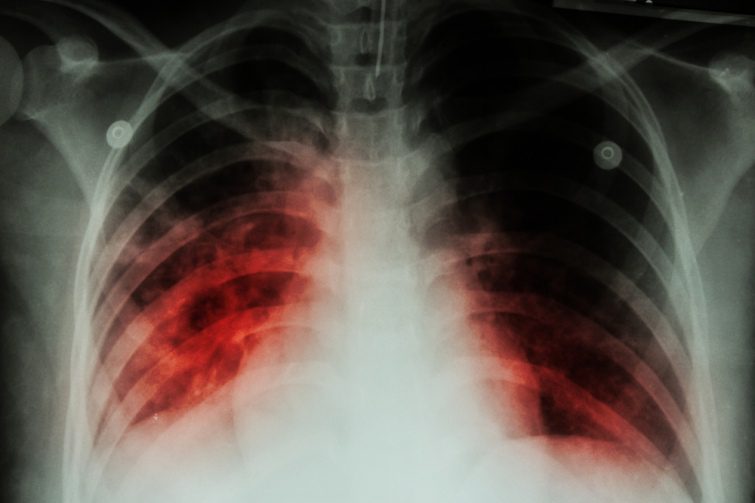

Туберкулез — это инфекционная болезнь, которую вызывает микобактерия туберкулеза. Заболевание протекает в хронической форме. Чаще всего поражает легкие, а в случае внелегочного туберкулеза могут поражаться другие органы: кости, кожа, мозг.

Чаще всего наблюдается сухой кашель, который не проходит в течение 3 недель. Во время сна больной очень потеет. В дневное время постоянно ощущает слабость, беспричинно теряет вес. У больных туберкулезом температура тела держится 37 градусов без видимой на то причины. Во время физической нагрузки возникает одышка, боль в грудной клетке.

Рентгенологическое обследование взрослые должны проходить раз в год. Если у человека есть сопутствующие болезни такие, как ВИЧ стоит проходить обследование, раз в полгода. Сделать это можно в любой больнице. Кроме того, бесплатно можно сдавать анализы мокроты в городских лабораториях.